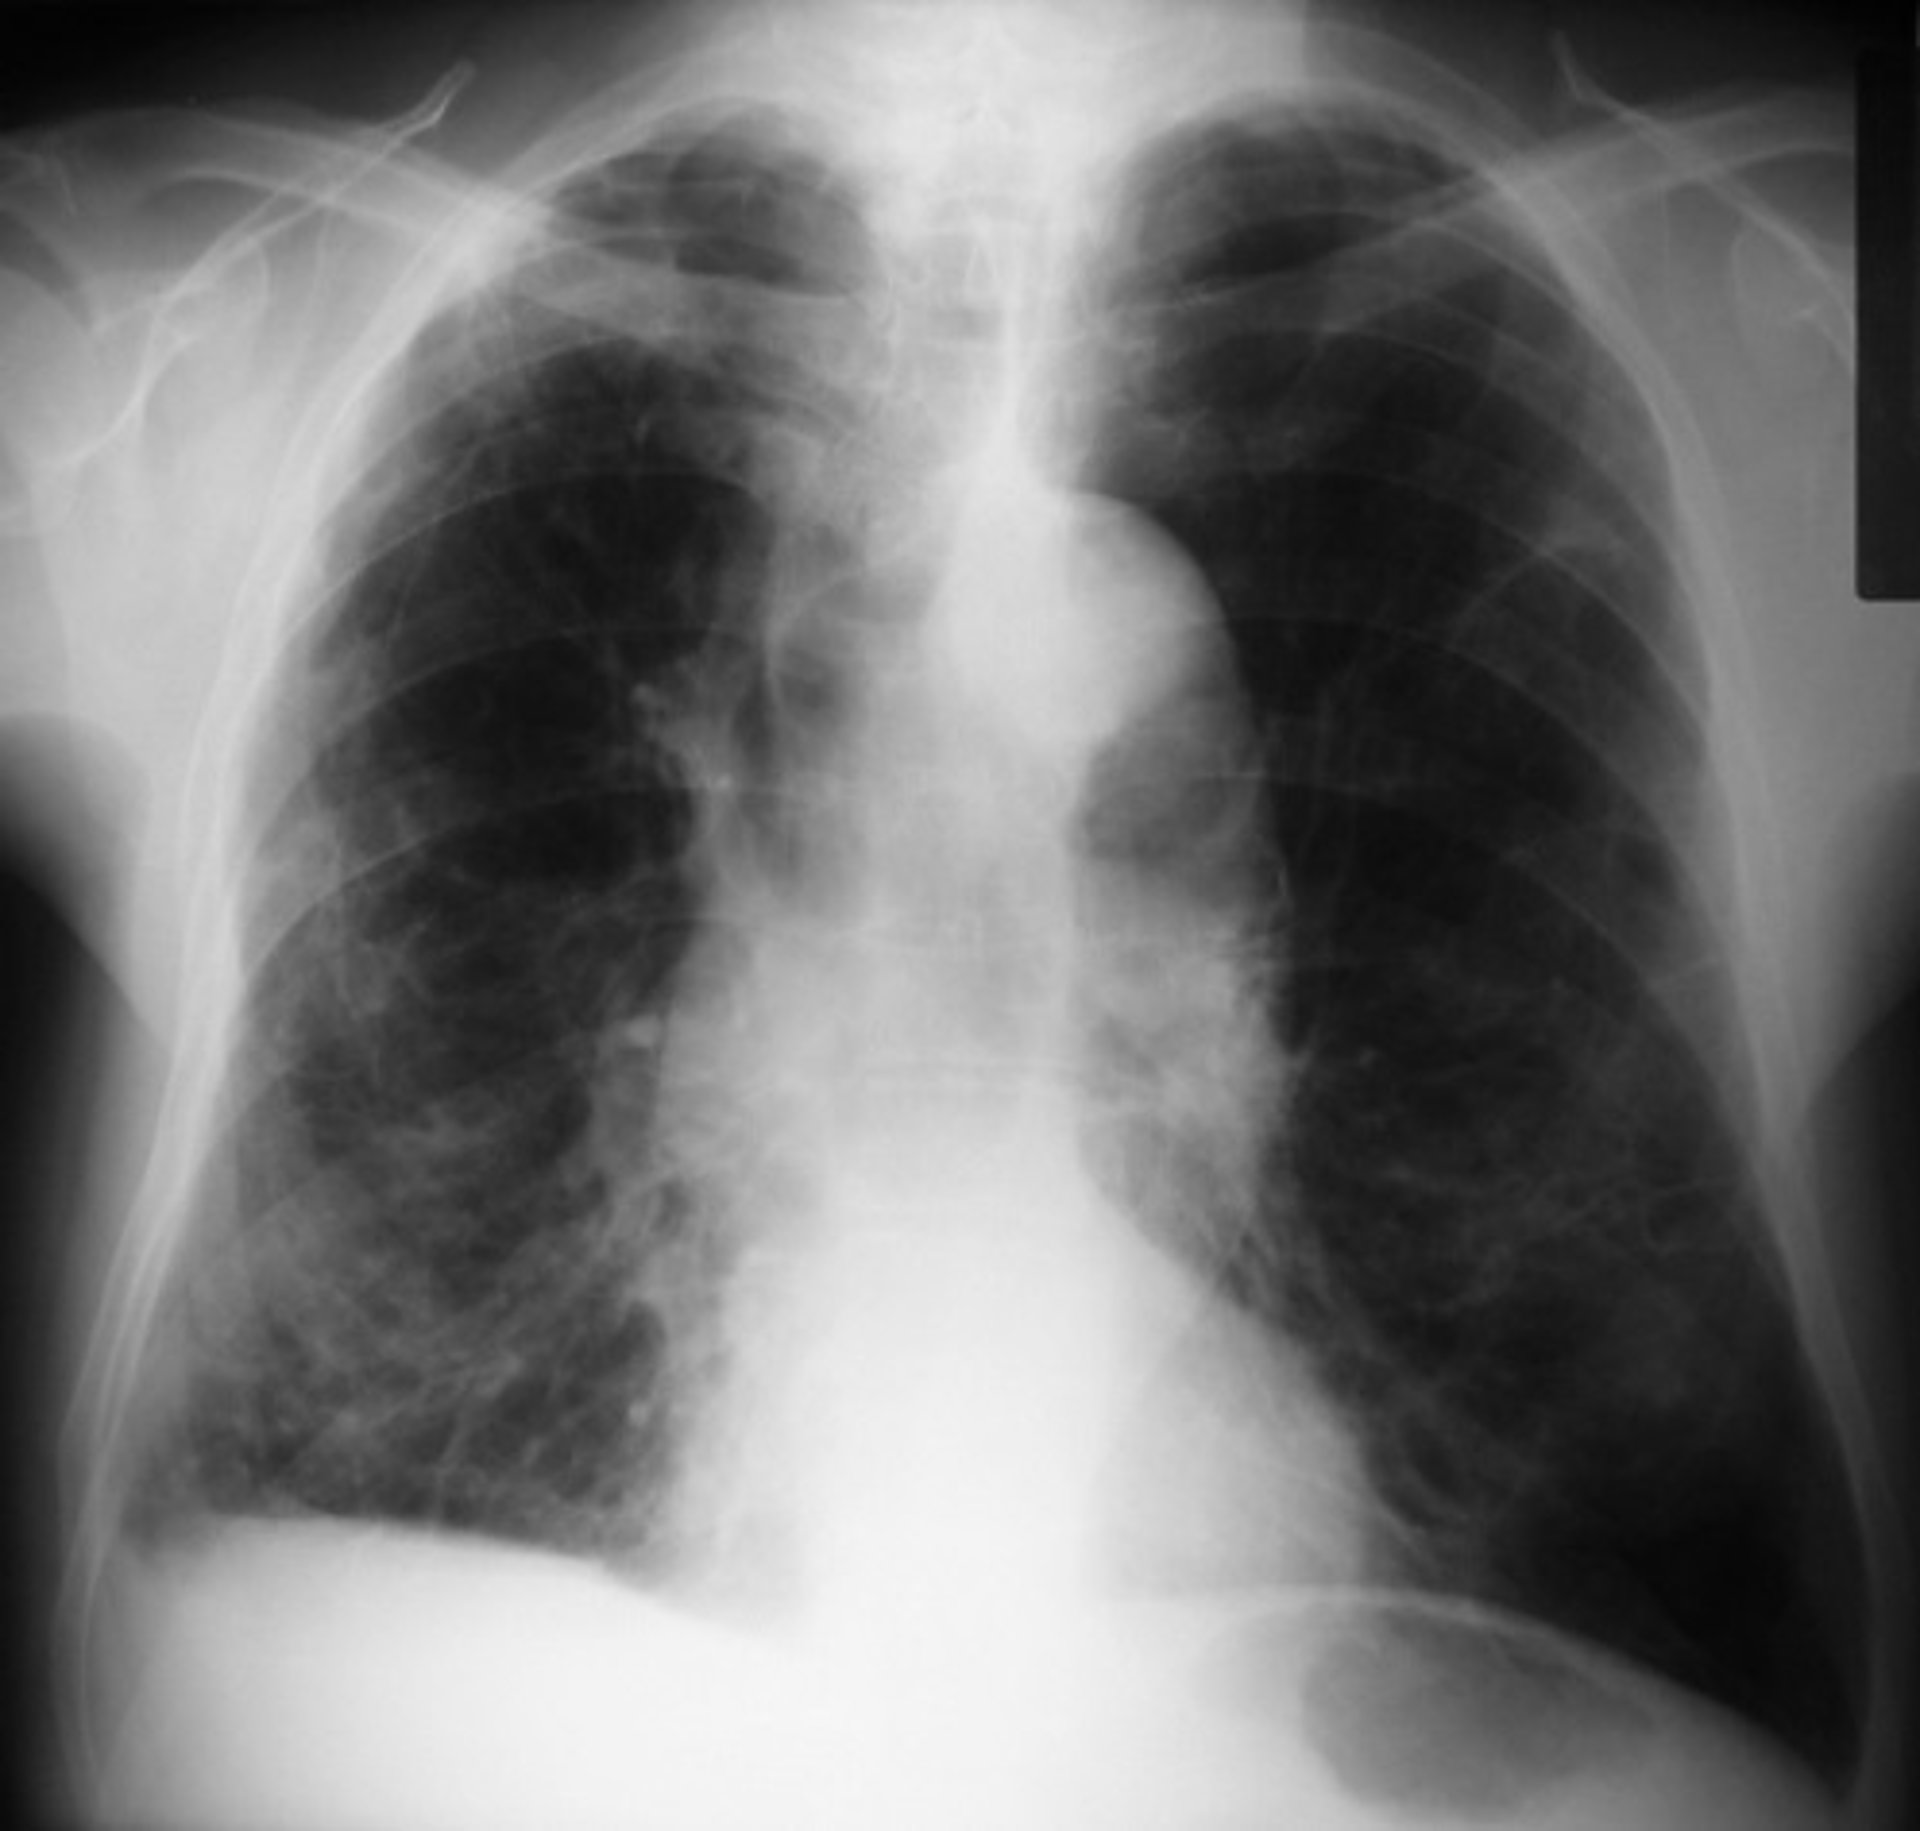

Un gran estudio mundial sobre la composición genética individual y el riesgo de desarrollar una enfermedad pulmonar podría permitir a los científicos predecir con más exactitud -en función de los genes y el tabaquismo-- su probabilidad de desarrollar enfermedad pulmonar obstructiva crónica (EPOC), una patología mortal que es la tercera causa más común de muerte en el mundo.

El avance podría ayudar a desactivar una "bomba de relojería" para la enfermedad pulmonar grave, con más de 1.000 millones de fumadores en todo el mundo en riesgo. La enfermedad pulmonar obstructiva crónica (EPOC) genera dificultad respiratoria y es la tercera causa más común de muerte en todo el mundo. En Reino Unido hay alrededor de 900.000 personas que viven con EPOC, lo que cuesta el sistema nacional de salud (NHS, por sus siglas en inglés) más de 800 millones de libras esterlinas al año y que cuesta a la economía 3.800 millones de libras en pérdida de productividad.

Fumar es un fuerte factor de riesgo para la EPOC, pero no todas las personas afectadas por la EPOC son fumadores y no todos los fumadores desarrollan la enfermedad, en gran parte, debido a la propia composición genética. La nueva investigación tuvo como objetivo descubrir la variación genética en el contenido de ADN de las células entre los individuos que se asocia con el riesgo de desarrollar enfermedad pulmonar.